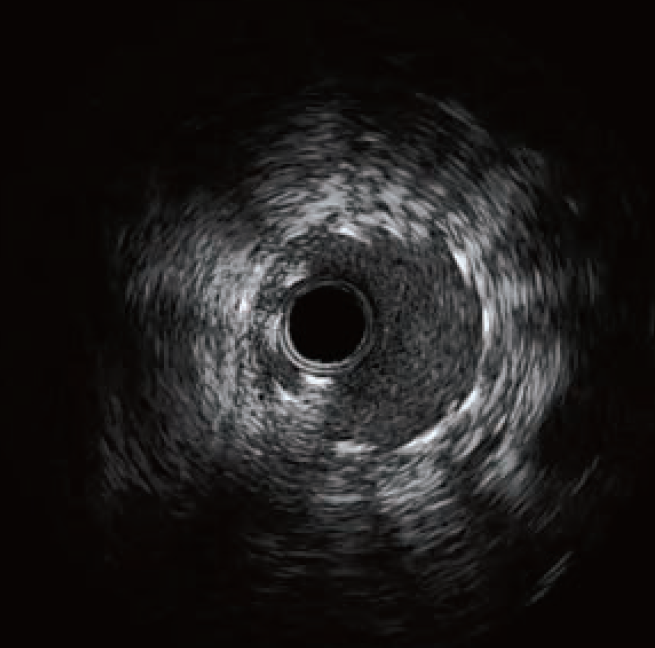

支架变形IVUS经典图

支架变形特点

支架变形及穿孔

支架变形指支架释放膨胀后在外力影响下改变原本柱状形态,包括纵向压缩、移位、横向形状改变等。